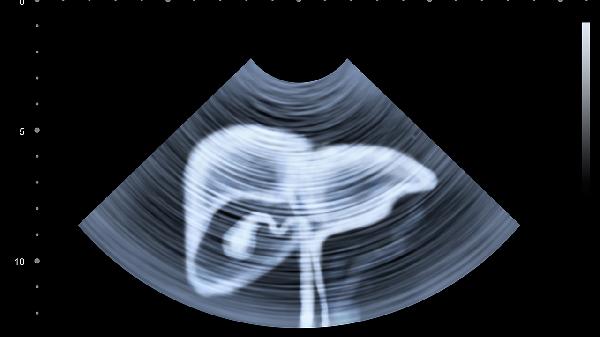

那位离世的患者最后一次复查时,超声显示肝脏已经布满肿瘤。主治医生摇头叹息:"明明三年前体检就提示脂肪肝,要是当时能改变生活习惯..."护肝没有捷径,今天少喝一杯酒,明天肝脏就少受一份罪。从今晚11点前睡觉开始,给自己一个重获新生的机会吧!